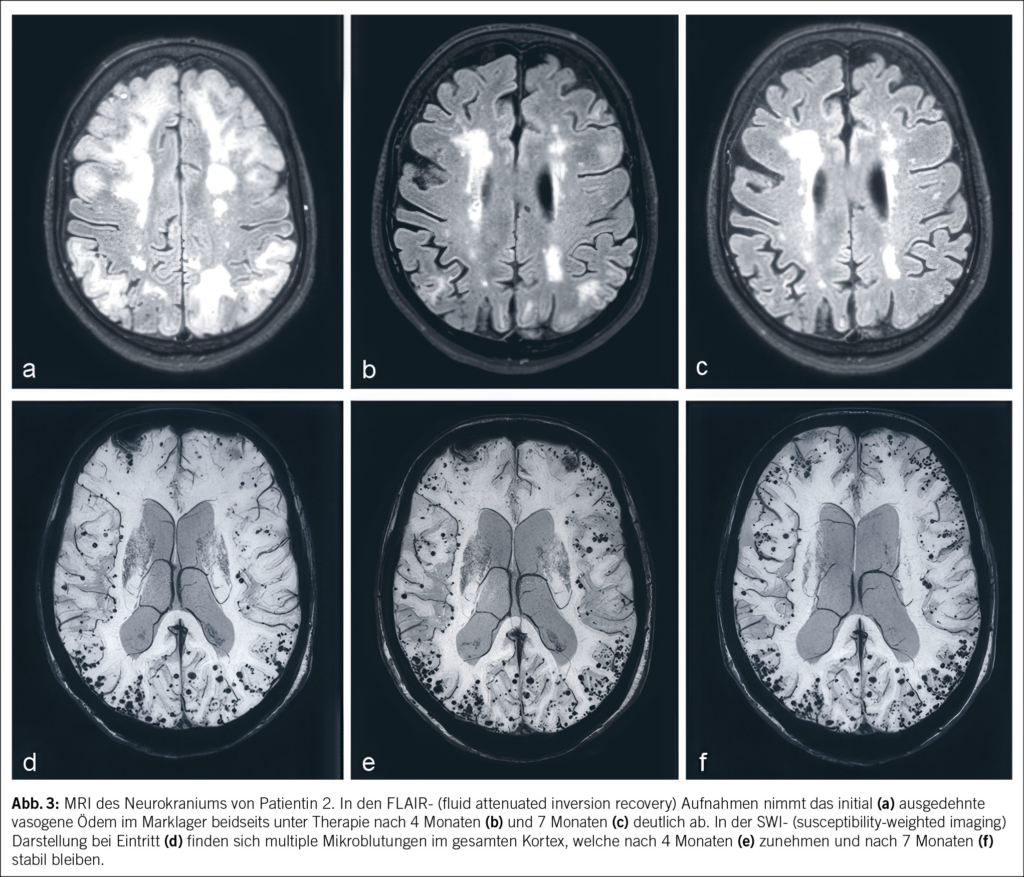

Eine 74-jährige Patientin wurde im Januar 2022 mit seit einigen Wochen fortschreitender Verwirrtheit, Verlangsamung sowie kognitiver Beeinträchtigung aus einem peripheren Spital in unsere Notaufnahme überwiesen. Ausserdem bestand ein progredienter Mutismus, welcher im Rahmen einer Trauersituation nach dem Tod des Ehemannes 1 Monat zuvor aufgrund von Covid-19 angesehen wurde. Die Patientin selbst litt an Covid-19 mit milden Symptomen. Nun zeigte das MRI des Neurokraniums eine ausgedehnte Leukenzephalopathie, ein vasogenes Ödem und mehrere Mikroblutungen (Abb. 3). Die Ergebnisse des Liquors waren negativ für Treponema pallidum und Lyme-Borreliose, ebenso eine Multiplex-PCR für Meningitis-Erreger. Die Immunphänotypisierung im Liquor, welche bei Verdacht auf ein Lymphom durchgeführt wurde, war negativ für B-Zell- und T-Zell-Neoplasien. Eine Bestimmung im Liquor von Beta-Amyloid, Tau-Protein und Phospho-Tau-Protein als Demenzmarker sowie Neurofilament-Leichtketten (NFL) als Marker bei Multipler Sklerose erfolgte nicht. Ebenso wurden die Biomarker GFAP und NFL serologisch nicht untersucht. Es wurde ein EEG angefertigt. Neben moderaten Allgemeinveränderungen und bifrontaler fokaler Verlangsamung fanden sich Epilepsieverdächtige Einzelpotenziale rechtshemisphärisch, welche unter Levetiracetam-Therapie nach 1 Woche abnahmen. Klinisch kam es jedoch noch zu keiner objektivierbaren Verbesserung. Die Patientin erzielte im MoCa-Test 12/30 Punkte, was für eine starke kognitive Beeinträchtigung steht. Schliesslich wurde eine Biopsie des Hirngewebes entnommen. Diese zeigte Veränderungen im Zusammenhang mit der Alzheimer-Krankheit mit Tau-positiven Neuronen, neurofibrillären Tangles und eine grosse Menge an Beta-Amyloid-Plaques sowie Amyloidablagerungen an den Gefässwänden (Abb. 4). Zusätzlich fanden sich subarachnoidal Zeichen einer wenige Tage alten Einblutung. Aufgrund der perivaskulären Entzündung wurde schliesslich eine cerebrale Amyloidangiopathie-assoziierte Entzündung (CAA-RI) als am wahrscheinlichsten angesehen. Eine Therapie mit Methylprednisolon intravenös 1 g/Tag gefolgt von oralem Prednisolon mit 1 mg/kg Körpergewicht wurde eingeleitet. Nach der Entlassung erfolgte eine stationäre neurologische Rehabilitation. Hier kam es zu einer klinischen Verbesserung mit jedoch relevanten Einschränkungen in Bezug auf die täglichen Routinen und das Kurzzeitgedächtnis. Die Prednisolon-Dosis wurde langsam reduziert.

In den Verlaufskontrollen bis August 2022 nahmen die Ödemareale im MRI des Gehirns weiter ab, und es fanden sich keine neuen Läsionen. Die multiplen Mikroblutungen supratentoriell beidseits und vereinzelt infratentoriell blieben stationär. Klinisch zeigte die Patientin weiter eine Besserung mit weniger anhaltenden Einschränkungen. Im MoCA-Test wurden 3 Monate nach Diagnosestellung und Therapiebeginn 15/30 Punkte und 7 Monate nach Diagnose 25/30 Punkte erzielt. Im November 2023 wurde eine neuropsychologische Testung durchgeführt, da die Patientin die Fahrtauglichkeit wieder anstrebte. Hier konnte eine Verbesserung der Grundaktivierung, allerdings aber auch eine relevante Verschlechterung der Aufmerksamkeitsteilung, objektiviert werden. Die kognitiven Defizite umfassten fronto-temporo-parietale Ausfälle, und es bestand ein unveränderter Unterstützungsbedarf im Alltag. Die Fahreignung konnte aus neuropsychologischer Sicht weiterhin nicht bestätigt werden. Auch wurde aufgrund der Befunde des letzten MRI des Gehirns von 2022 von keiner weiteren Regredienz der kognitiven Defizite ausgegangen.

Die Amyloidablagerungen sind bei einem Teil der Patienten mit einer Entzündung der Gefässwand vergesellschaftet, was schliesslich zu einem multifokalen Marklagerödem führt. Insgesamt zeigen diese Veränderungen im MRI ein typisches Bild, welche für die Diagnosestellung einer CAA-RI wesentlich sind. Die Veränderungen lassen sich vor allem in der FLAIR-Sequenz (fluid attenuated inversion recovery) und bei der SWI (Suszeptibilitätsgewichtete Bildgebung) feststellen (2, 3). Dazu gehören Mikroblutungen, eine kortikale superfizielle Siderose und eine asymmetrische fleckförmige oder konfluierende Leukenzephalopathie, welche den angrenzenden Kortex und das subkortikale Marklager miteinbeziehen können. Ebenfalls kann sich als Zeichen der entzündlichen Reaktion ein vasogenes Ödem in der ADC- (apparent diffusion coefficient) Wichtung präsentieren (2, 4, 5). Es wurden die sogenannten modifizierten Boston-Kriterien entwickelt, welche auf eine gute Sensitivität und Spezifität geprüft wurden (6) (Tab. 1) und bei der Diagnosesicherung helfen. Zusätzliche klinische Diagnosekriterien sind ein akuter/subakuter Symptombeginn, Alter über 55 Jahre, Symptome wie Kopfschmerzen, Wesensveränderungen, kognitive Defizite oder fokal neurologische Defizite oder epileptische Anfälle. Andere Ursachen (z. B. infektiös oder paraneoplastisch) müssen ausgeschlossen werden. Sind alle diese Kriterien erfüllt, gilt eine CAA-RI als wahrscheinlich. Zur definitiven Diagnosesicherung wird eine histologische Bestätigung im Rahmen einer Autopsie benötigt, wobei sich neben frischen und alten Ischämien und Einblutungen auch entzündliche, perivaskuläre Veränderungen ohne Gefässbeteiligung finden lassen. Hier kann eine Unterscheidung zur Beta-Amyloid-assoziierten Angiitis (ABRA) gemacht werden, welche ausgeprägtere vaskulitische Veränderungen und fibrinoide Gefässwandnekrosen zeigt. Diese erheblichen Zerstörungen des Hirnparenchyms direkt durch invasive zytotoxische T-Lymphozyten und indirekt durch vaskulitische oder begleitthrombotische Gefässverschlüsse bedingen eine stärkere Immunsuppression als bei der CAA-RI. Teils wird in der Literatur jedoch die ABRA synonym zur CAA-RI genannt. Ob eine Histologie zur Diagnosestellung einer CAA-RI immer zwingend ist, steht aktuell immer noch zur Diskussion. Eine genaue Diagnose hat jedoch teils therapeutische Konsequenzen. Vor allem bei fehlendem Therapieansprechen sollte eine Biopsie angestrebt werden.